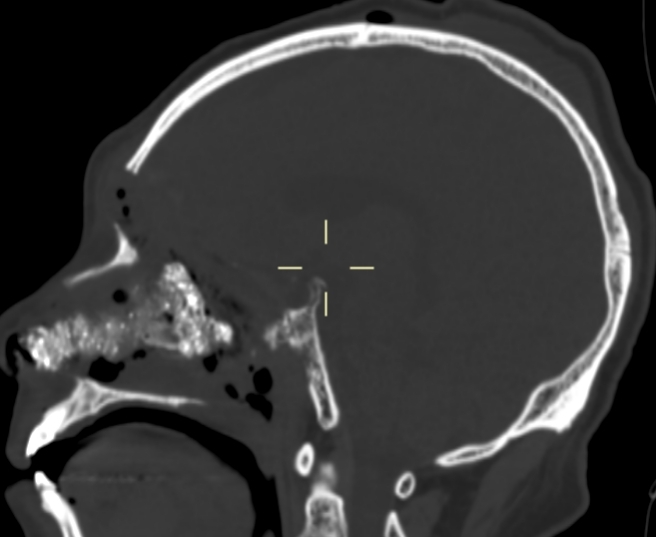

我院PET-CT检查显示鼻咽周围骨质改变,未见异常代谢增高,无肿瘤复发;左侧颞叶、左侧岛叶及左侧鞍旁片状低密度影,伴代谢稀疏,提示放射性坏死。脑室造影检查显示颅内积气,前颅底鞍结节颅骨缺损,脑脊液漏可能(图1-3)。MRI检查显示左侧颞叶内侧面不规则强化病灶,考虑放射性脑坏死改变(图4)。